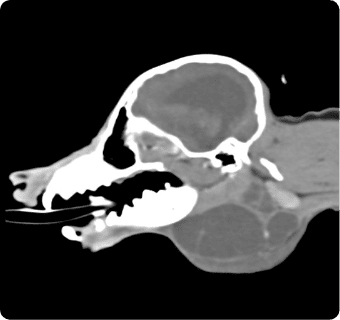

진단하는 핵심센터입니다. 고화질 CT와 초음파, 디지털 엑스레이, 투시촬영기기(C-arm)을 사용해

고해상도 영상과 정밀한 분석을 통해 질병의 조기 발견과 맞춤 치료 방향 제시를 목표로 합니다.

빠른 촬영속도를 통해 마취시간을 최소화 하며, 선명한 3차원 영상을 구현합니다.

종양, 전이평가, 선천적 혈관 기형 등 여러 질환의 조기 발견 및 환자상태를 평가합니다.

이도(외이염, 중이염), 뇌수두증, 비염, 치과질환, 두경부 종양, 비강종양, 침샘질환